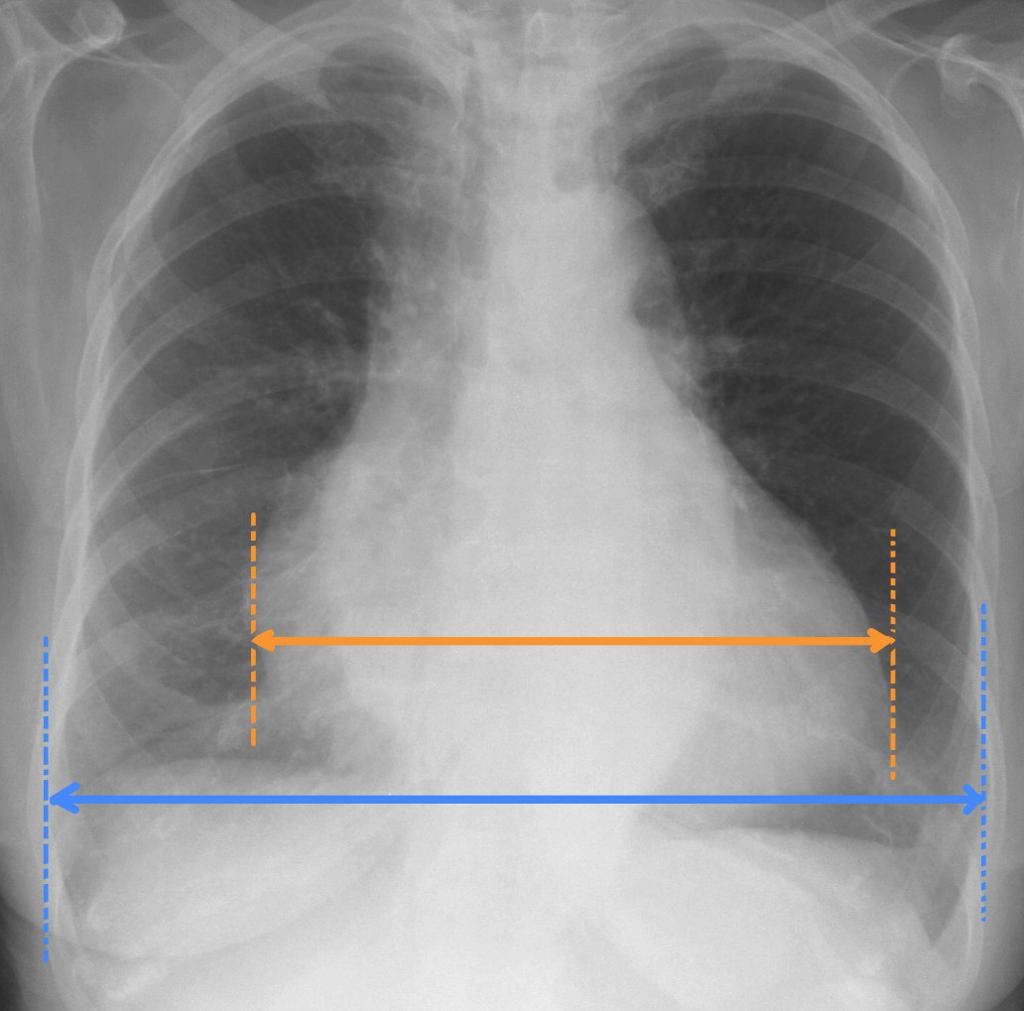

• Cardiothoracic ratio is measured on a PA chest x-ray, and is the ratio of:

- maximal horizontal cardiac diameter

- maximal horizontal thoracic diameter (inner edge of ribs / edge of pleura)

• A normal measurement should be less than 0.5.